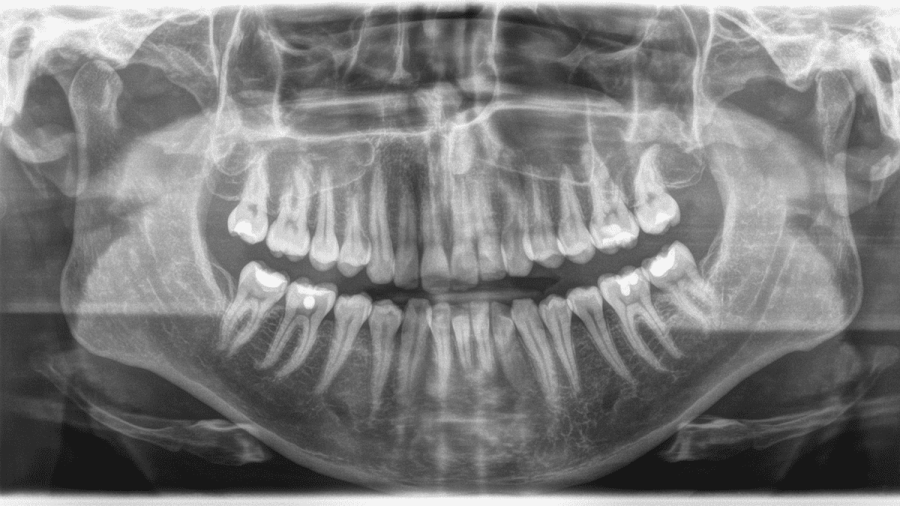

Technique 2D fournissant une vue d'ensemble des dents, des mâchoires, des sinus et des articulations temporo-mandibulaires (ATM) en une seule image.